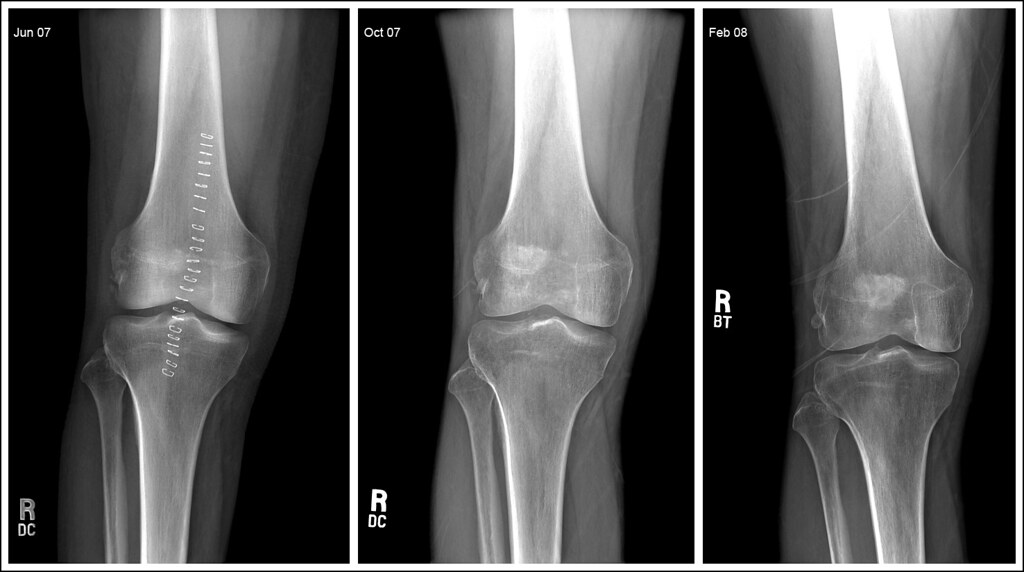

무릎연골 연화증 진단은 슬개골의 정렬 상태를 측정하거나,

무릎 관절 방사선 검사, 보행검사, 초음파 등 다양한 방법을 통해서도 가능하다.